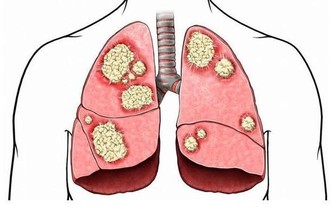

另從中醫的觀點來看,過貓菜也是很好的健康菜。黃慧娟中醫師表示,過貓屬於蕨類蔬菜,屬性偏寒,入大小腸經,具有清熱解毒和利尿的功效,可用於治療痔瘡和因細菌感染引發的腹瀉。不建議生食或直接榨汁來喝,以免對腸胃造成負擔;最好熟食或是汆燙後再吃,料理時最好搭配薑片或薑絲,可中和寒性。另,腸胃功能差或虛冷體質的人,不適合食用。